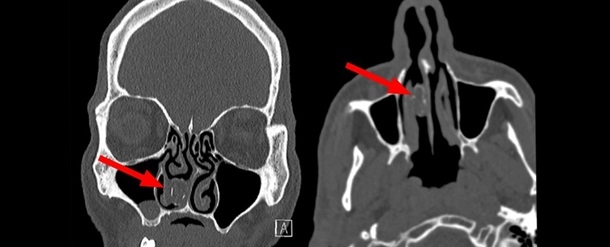

Под наркозом из ноздри пациента врачи изъяли камень ринолит. Внутри него оказалось растение.